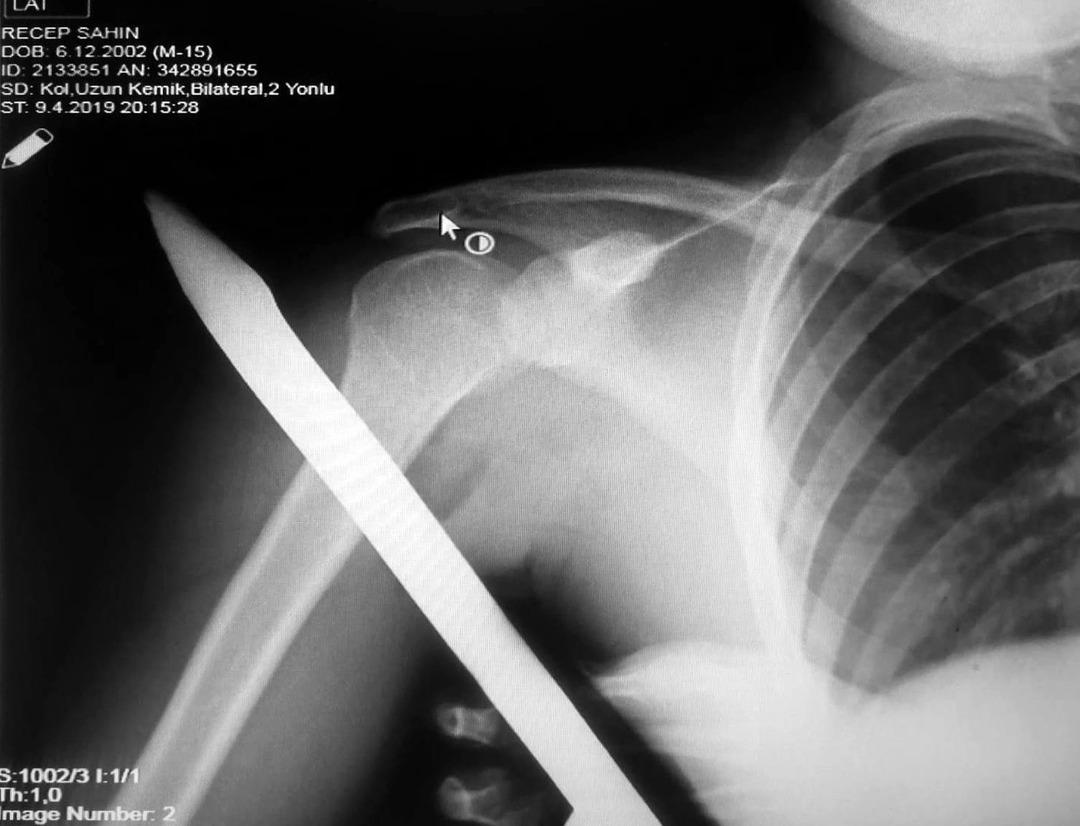

Asarcık ilçesi Emirmusa Mahallesi’nde dün meydana gelen olayda, Recep Şahin (17), cami çevresindeki korkulukların üzerinden atlarken ayağının kayması sonucu sivri uçlu demir omzuna saplandı.

Demir, gencin omzunun arkasından girip ön kısmından çıktı.

İhbar üzerine olay yerine gelen itfaiye, demiri keserek genci kurtardı. Genç, omzundaki demirle OMÜ Tıp Fakültesi Hastanesine kaldırıldı. Ortopedi ve Travmatoloji Uzmanı Prof. Dr. Turgut Nedim Karaismailoğlu tarafından yapılan başarılı operasyonla gencin omzundaki demir çıkarıldı.

Yaşadığı olayı anlatan Recep Şahin, “Caminin çevresindeki korkuluğun üzerinden atlarken ayağım kaydı. Korkuluk demiri omzuma saplandı. Demir omzumun arkasından girip önünden çıktı. Babamı aradım. İtfaiyeden yardım istedik. İtfaiye demiri kesti. Hastaneye kaldırıldım” dedi.

OMÜ Tıp Fakültesi Öğretim Üyesi Prof. Dr. Turgut Nedim Karaismailoğlu ise “Hastamızın ayağı kaymış ve korkuluk demiri omzuna saplanmış, arkadan girip önden çıkmış. Geldiğinde demirin ucu dışarıdaydı. Omzuna hasar vermiş.

Demiri omzuna zarar vermeden çıkardık. Damar ve sinir problemi olmadan hallettik. Bu korkuluk demirlerinin daha dikkatli yapılması gerekiyor. Sivri uçlu olduklarından böyle vakalar olabiliyor. Vatandaşlarımız bu konuda dikkatli olmalı” diye konuştu. (İHA)